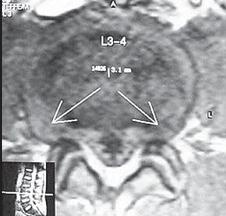

На МРТ № 11 наблюдается парамедианная грыжа межпозвонкового диска, которая как бы обхватывает с двух сторон спинной мозг На МРТ № 12 наблюдается медианная (срединная) грыжа межпозвонкового диска, которая часто протекает безсимптомно и может достигать больших размеров МРТ № 13 ![]() МРТ № 14

На МРТ № 13 наблюдается медиолатеральная грыжа межпозвонкового диска (заднебоковая) На МРТ № 14 наблюдается фораминальная грыжа межпозвонкового диска с локализацией внутрь межпозвонкового отверстия МРТ № 15 ![]() МРТ № 16